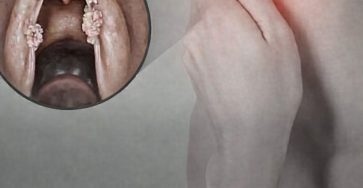

Quels sont les symptômes du VPH dans la gorge ?

Cancer du pharynx (1/10) La célèbre chanteuse française Françoise Hardy est décédée le 11 juin 2024, à l'âge de 80…